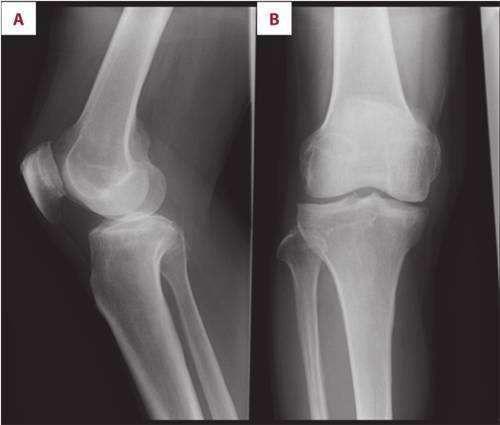

怎么治疗膝关节骨性关节炎

相关图片